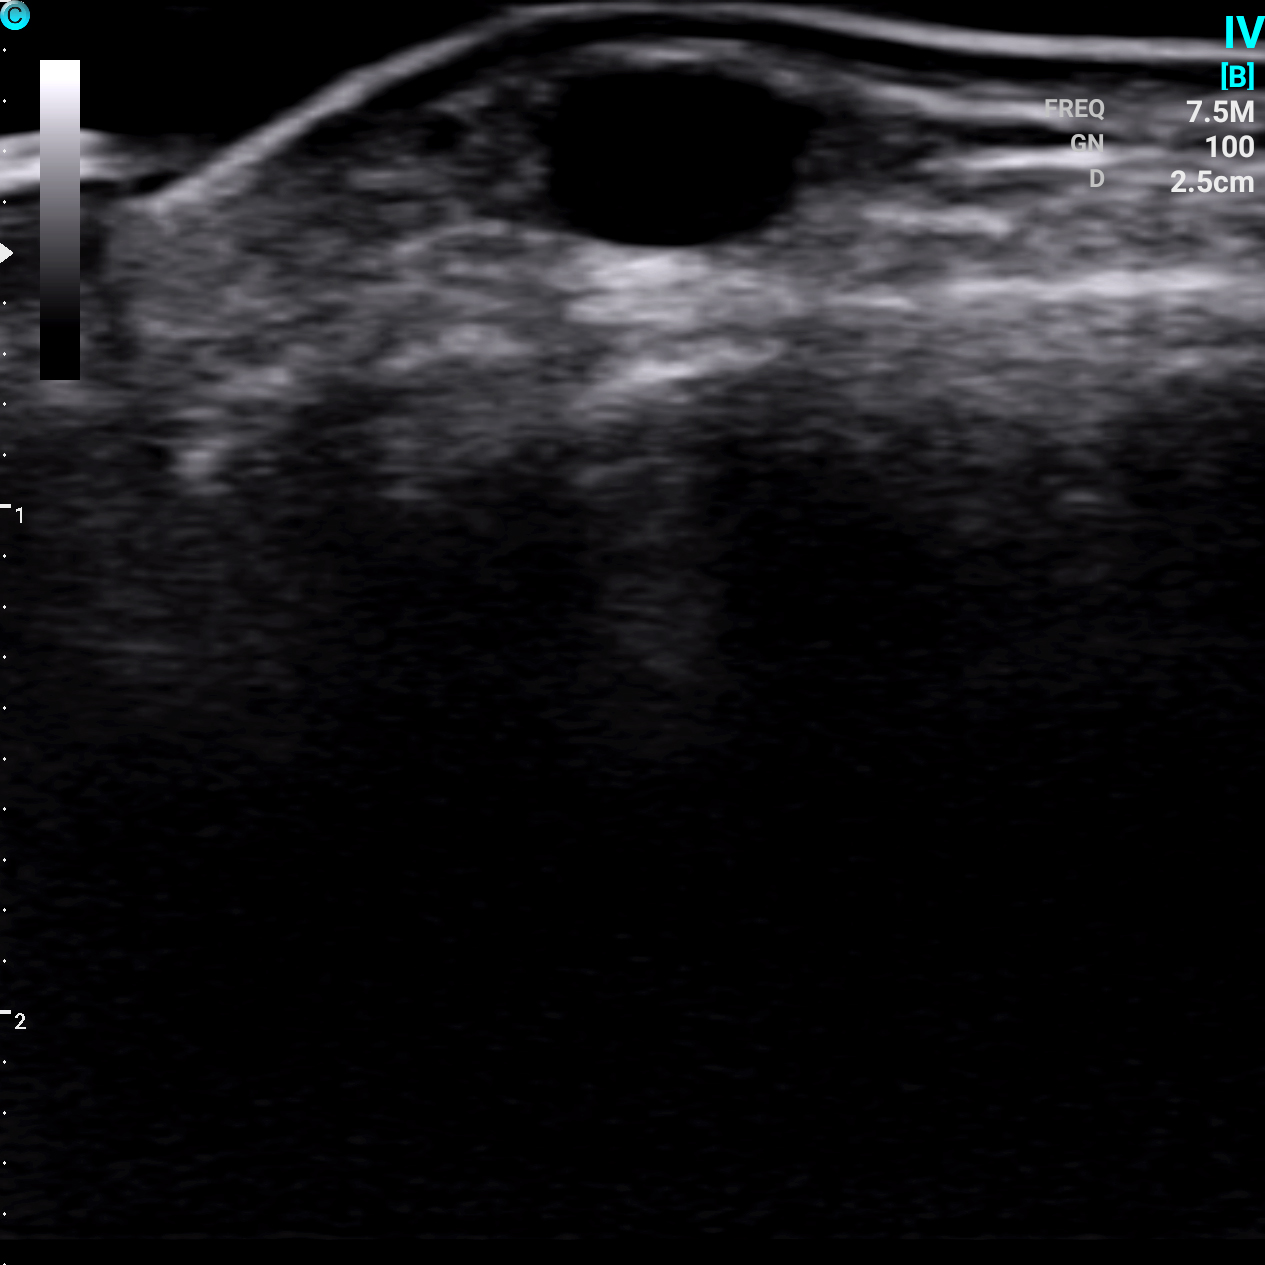

颈内静脉 B模式

静脉 B模式